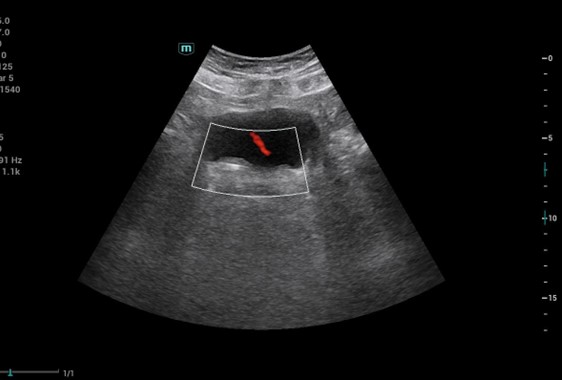

Manejo de cólico nefrítico con hidronefrosis grado II en hombre de 63 años y situación familiar compleja que impide manejo hospitalario.